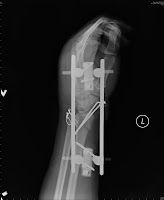

Big Bad: Tension band wiring for ulnar styloid process ...

Big Bad: Tension band wiring for ulnar styloid process ... from 1.bp.blogspot.com